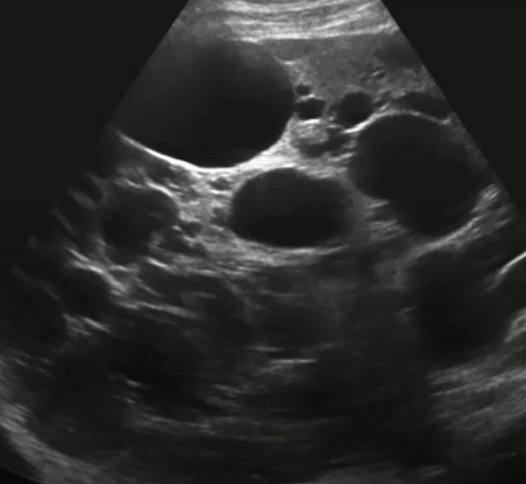

If a patient has autosomal dominant polycystic kidney disease, what will that look like?

Kidneys become enlarged and are slowly replaced by large cysts

Autosomal dominant polycystic kidney disease

When is autosomal dominant polycystic kidney disease usually diagnosed?

30s-40s

Hypertension and renal failure

___% of patients with autosomal dominant polycystic kidney disease will also have ___ ___

50, liver cysts